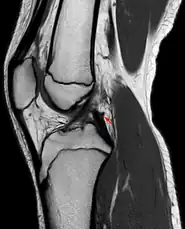

Posterior meniscofemoral ligament (Wrisberg) behind the posterior horn of the lateral meniscus close to its insertion. Sometimes wrongly interpreted as a meniscal tear.